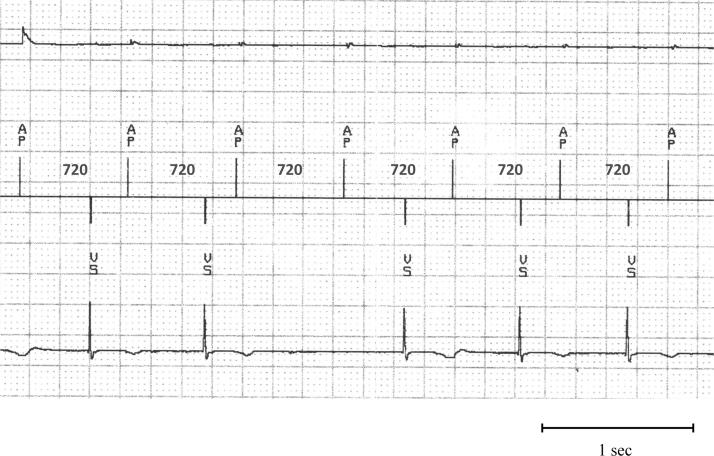

Tachycardia-induced cardiomyopathy long after a pacemaker implantation for the treatment of unusual 2:1 atrioventricular block: What is the mechanism?

HeartRhythm Case Rep. 2015 Oct 20;2(1):107-110. doi: 10.1016/j.hrcr.2015.09.009. eCollection 2016 Jan.